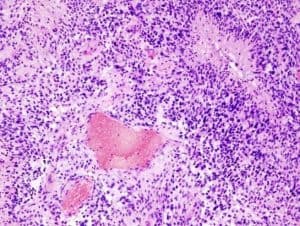

تُوفي السيناتور جون ماكين في 25 أغسطس الماضي بعد عامٍ من الخضوع لعلاج الورم الأرومي الدبقي، وهو نوع شديد العدوانية…